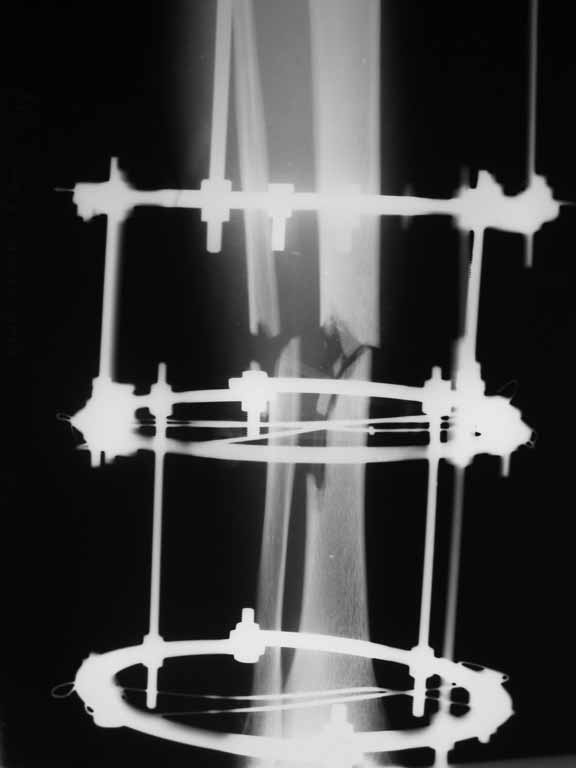

Re: Перелом большеберцовой кости с дефектом дифизарной части

Внедрение одного отломка в другой приведет к укорочению. Резекция с выращиванием резко удлинит срок лечения, вероятно, потребуются еще какие-то операции после завершения дистракции... А самое главное, это избыточные действия. Ведь дефект не сегментарный, краевой контакт есть.

Вполне достаточно закрытого интрамедуллярного остеосинтеза без открытых вмешательств в зоне стыка. Конечно, с рассверливанием. Если есть опасения насчет инфекции, то на гвоздь нанести цемент с ванкомицином.

Гвоздь тут будет эндопротезом диафиза на достаточное время для образования сращения в зоне имеющегося небольшого контакта. И далее страховкой от рефрактур.

Вот пример, тоже открытый перелом, первичный дефект, пробыл в аппарате 5 мес. Титановый гвоздь, сразу динамический, без покрытия. Больше не делали ничего.